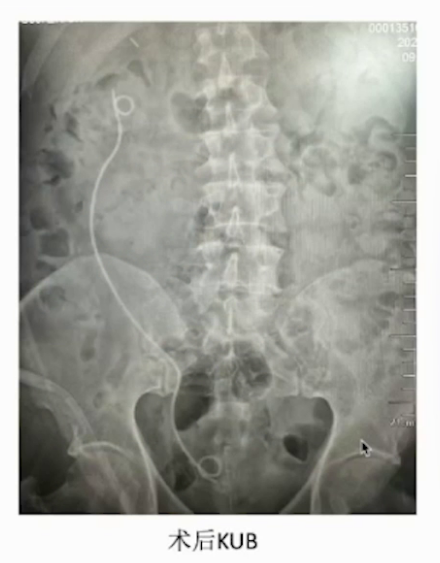

(1)行右侧输尿管软镜碎石取石术

因手术时间长、结石负荷大且尿液感染,遂在击碎部分结石后放置双J管并终止手术。

(3)2周后行右侧PCNL,取出结石

2周后,鉴于患者结石负荷大,行B超引导下经皮肾镜取石术。该结石为X线及CT阴性结石,成功穿刺右肾上盏后,打造影剂显示集合系统有明显充盈缺损,结石表面黄褐色。使用气压弹道轻易击碎结石,并通过负压吸引取出。